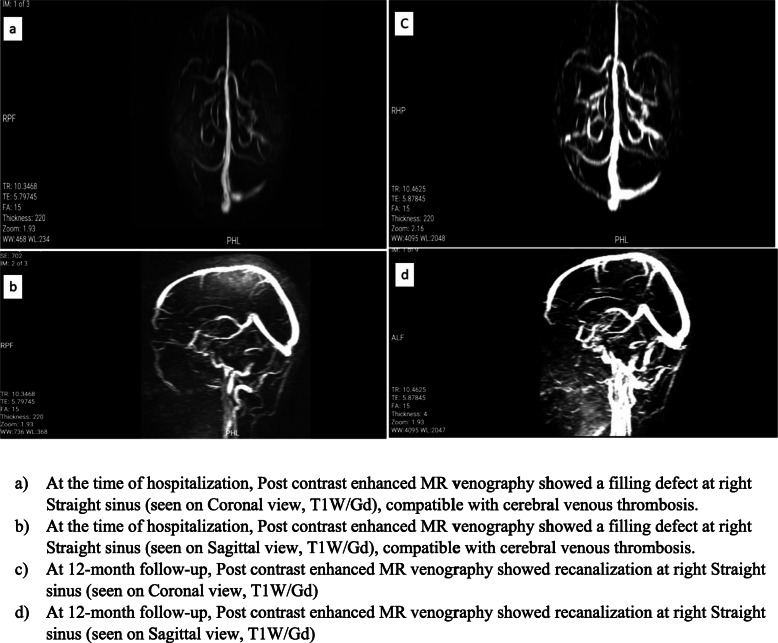

In this retrospective study, we included 36 patients admitted to a central neurology hospital affiliated to Iran University of Medical Sciences, Tehran, Iran from 2017 to 2020 with cerebral venous/sinus thrombosis. The diagnosis had been confirmed by filling defects at sinuses on post-contrast enhanced Brain MR venography (MRV) (Fig. 1 a,b). Initial relevant demographic data and clinical features including predisposing factors, clinical findings, imaging characteristics, the prescribed anticoagulant drug at the time of hospitalization, and discharge were obtained from patients’ documents. Classification of patients with hemorrhagic brain lesion were done according to European Cooperative Acute Stroke Study (ECASS) [17].

Fig. 1.

Contrats-enhanced Magnetic Resonance venography of a patient with Cerebral Venus Thrombosis (CVT). At the time of hospitalization and at 12-month follow-up. a. At the time of hospitalization, coronal (a) and sagittal (b) contrast-enhanced MR venography showed a filling defect in the right transverse sinus, compatible with cerebral venous thrombosis. At 12-month follow-up, coronal (c) and sagittal (d) contrast enhanced MR venography showed recanalization of right transverse sinus

Patients were divided into two groups according to oral anticoagulant (Warfarin vs. Rivaroxaban). Patients’ follow-up began 12 months after the hospitalization period. They were followed up for treatment assessments and possible side effects through face-to-face evaluation by a staff neurologist. Follow-ups included clinical evaluation in terms of modified Rankin Scale (mRS), and inquiry about the occurrence of any other events of CVT during therapy. Furthermore, the occurrence of any type of bleeding was noted. In cases of bleeding, the severity and complications were assessed.MRS 0 or 1 were considered as favorable outcome [15]. 3 patients were missed to follow-up, thereby were not included in the final analysis. Similarly, the final contrast-enhanced brain MR venography was assessed for detecting recanalization. (Fig. 1 c,d) The MRV results were categorized into two groups of complete and partial recanalization. Subsequently, both groups were compared in terms of the final outcomes and side effects.